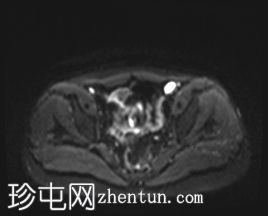

MRI

左侧阴囊空虚。

左侧睾丸位于盆腔左侧前壁,腹股沟管上方。其体积较小(与对侧正常的右侧睾丸相比)。T2加权像呈高信号,T1加权像呈低信号,未见明显局灶

性病

变。

右侧睾丸位于右侧阴囊内,大小和形状正常。